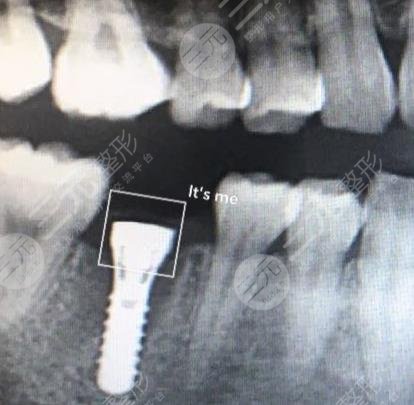

I am a lecturer in the company, usually I may have to face the whole company for training, so the requirements for appearance are relatively high, because not long ago I lost a tooth, resulting in the whole appearance has also been affected, and when I speak, it is also very uncomfortable, so I have always wanted to carry out dental restoration, and later under the introduction of a friend, I found a local well-known dental hospital, in fact, when I was looking for a hospital, I also learned some related methods of repairing teeth, in fact, I am more inclined to dental implants After coming to the hospital, I didn't expect the doctor to recommend dental implant surgery to me.

The price of dental implants may be relatively high, but I know that the results are better, and the maintenance time will be longer, it can be said that it can bring a one-time treatment, before doing dental treatment, the doctor also introduced me to some related knowledge, I know a lot, during the operation injected anesthetic, so I will not feel pain at all, this is not to worry. When I just had dental implant surgery, I may feel some swelling, and there will also be bleeding, I was like this at the time, and the doctor who was still worried at that time told me some relevant details for me to pay special attention to, this situation is normal, generally it will slowly disappear in about 3 to 5 days, and if it is really on the 4th day, my tooth swelling will slowly disappear.

(Click here!) Free online consultation price)

It has been more than two months since I had dental implant surgery, because the time period of dental implant surgery is very long, but according to the good results, the whole tooth is better, and I can chew food normally, just like my own real teeth, I am more grateful to the doctor for the help I have brought to me, of course, I am also glad that I chose this hospital, I have many friends with bad teeth around me I also recommended them to come to this hospital for treatment, I believe that I will be able to get better dental restoration.